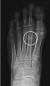

To get a better understanding of what is happening inside your foot, imaging tests may be necessary.

An MRI scan can detect a stress fracture in its early stages, even before an X-ray, however X-rays will often be taken first.

MRI scans are more sensitive than x-rays, which can only detect stress fractures after the healing process has begun.